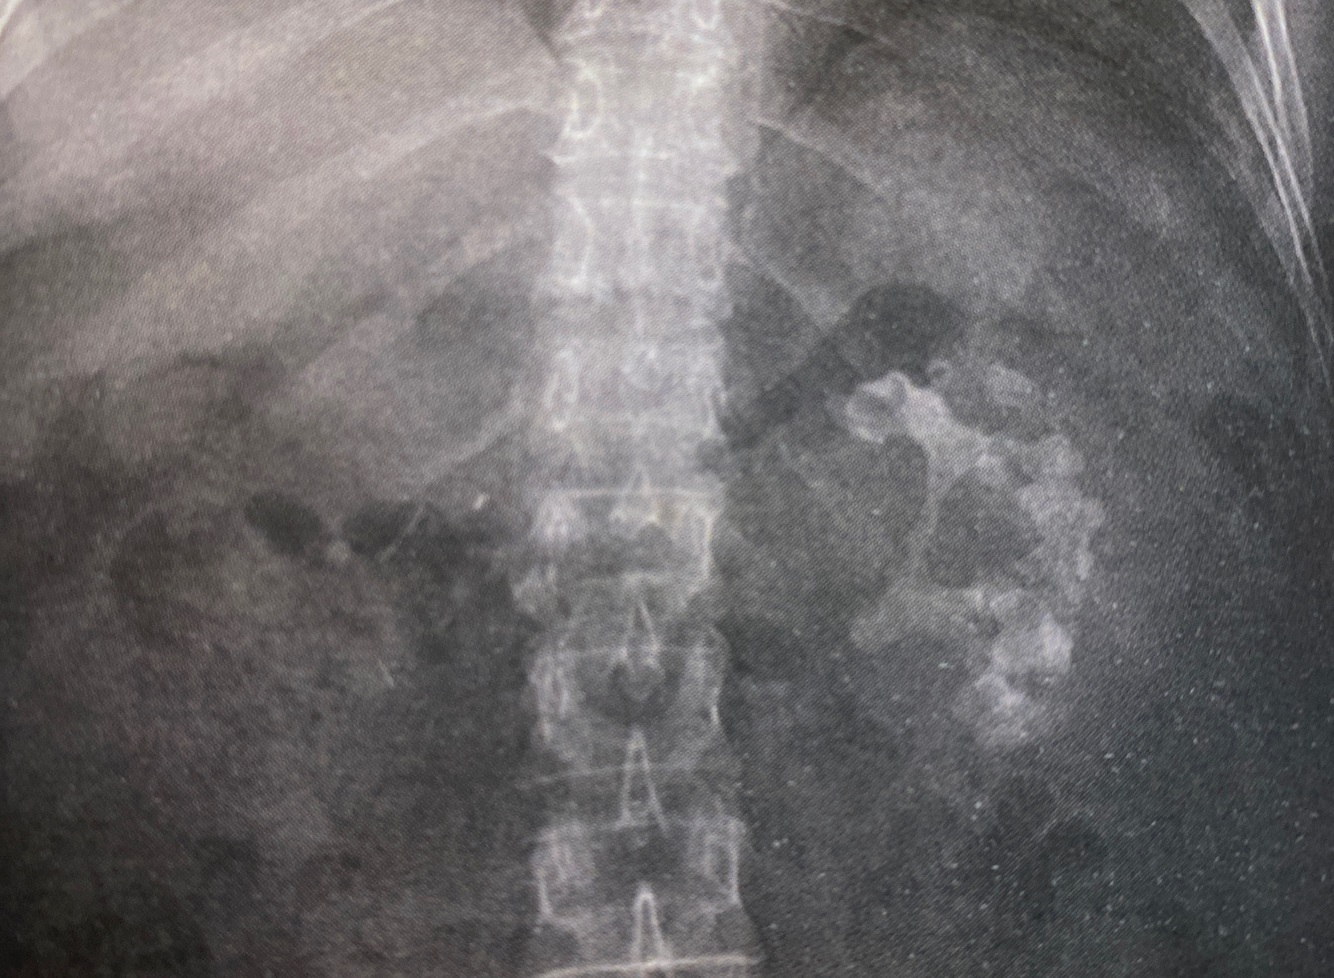

15

Q

A

Calculos coraliformes en la litiasis por proteus sobretodo ( también en la litiasis de cistina )